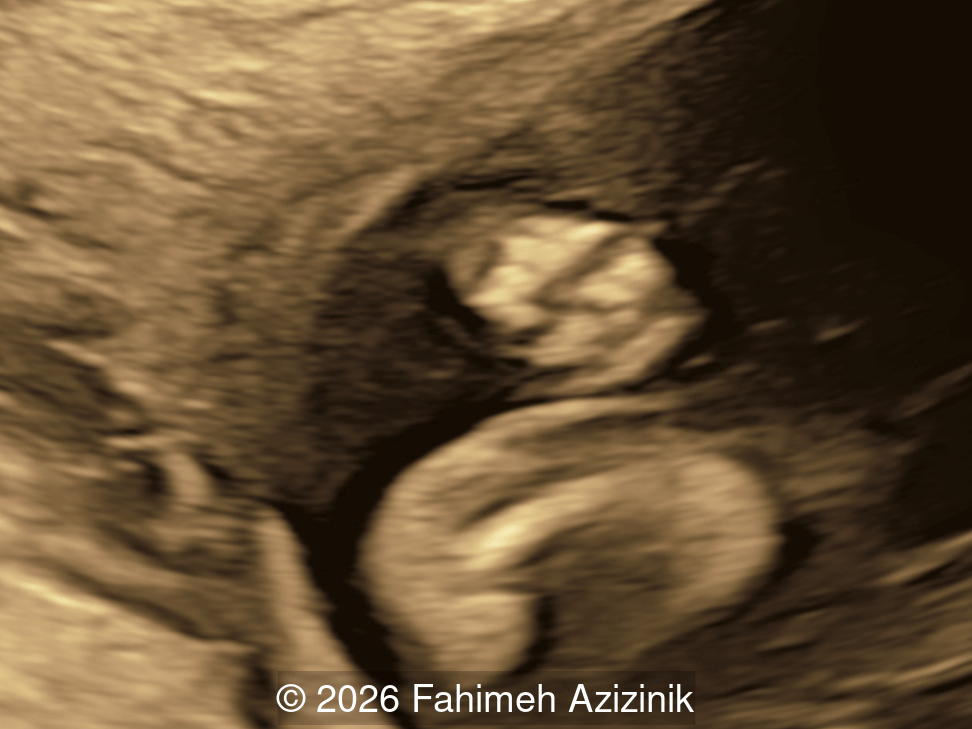

Image 3

Image 4

• Complex syndactyly of the hands and feet. Complex hand brachysyndactyly with “mitten-like” appearance due to bony fusion of the fingers

Bicoronal synostosis is the characteristic cranial hallmark of Apert syndrome, detectable sonographically from 18 weeks. Its most recognizable manifestation is turribrachycephaly, defined by an elevated cephalic index (typically >85–90%) and a tall cranial vault with marked frontal bossing [19]. On prenatal ultrasound, the face in Apert syndrome shows midface hypoplasia with a depressed nasal bridge, proptosis, hypertelorism, and frontal bossing. The extremities demonstrate syndactyly of both bone and soft tissue of the hands and feet with partial-to-complete fusion often involving second, third, and fourth digits, known as “mitten hands” and “socked feet”. In severe cases, all digits are fused, with the presence of a single nail known as “synonychia” [20]. Other ultrasound findings include mild ventriculomegaly, agenesis of the corpus callosum, deficient or absent septum pellucidum, and fusion of the cervical vertebrae at the level of C5-C6 [21]. Cardiovascular (atrial and ventricular septal defect) and genitourinary anomalies (hydronephrosis, and cryptorchidia) are present in 10% of patients [22]. Increased nuchal translucency in the first trimester [23], widely open metopic suture [24], and polyhydramnios [25] have also been reported. Three-dimensional (3D) ultrasound facilitates assessment of surface abnormalities of the face and extremities, and magnetic resonance imaging (MRI) can be used to evaluate associated intracranial conditions [26].